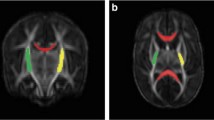

Term infants (control), premature infants without (normotypic) and with perinatal HIE (HIE) underwent brain magnetic resonance imaging at term-equivalent age (TEA) and at 2 years. Cerebrum, cerebellum, brainstem divisions and ventrodorsal compartments volumetric analysis were performed, as well as fractional anisotropy (FA) and apparent diffusion coefficient (ADC) of corticopontine, corticospinal pathways and middle cerebellar peduncles. Amiel-Tison scale at TEA and the Hempel test at 2 years were assessed.

Cerebellum, brainstem and its compartments volumes were decreased in normotypic and HIE groups at TEA, while at 2 years volumes were significantly reduced in the HIE group, accompanied by decreased volume and FA and increased ADC of corticopontine and corticospinal pathways. Negative association of the brainstem, cerebellum, mesencephalon, pons, corticopontine volumes and corticospinal pathway FA at TEA with the neurological score at 2 years. Cerebellum and pons volumes presented as potential prognostic indicators of neurological outcomes.